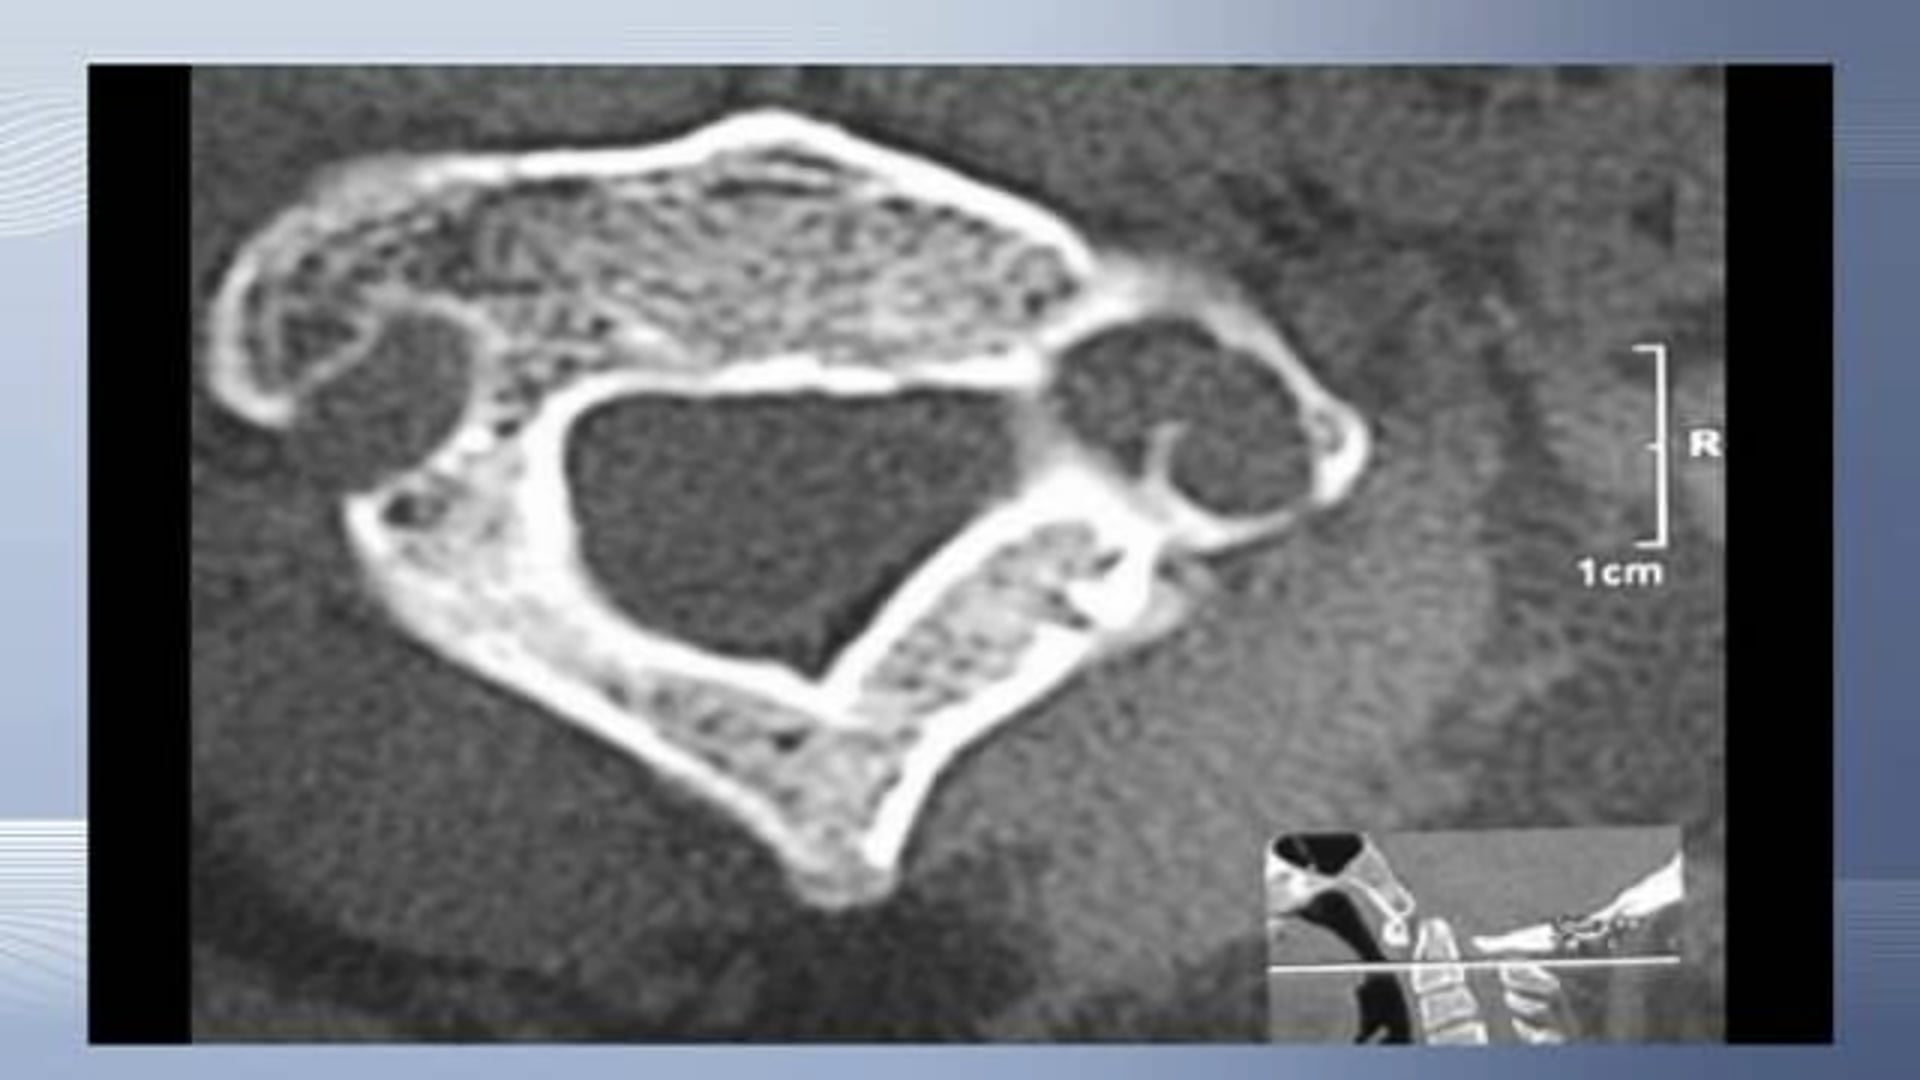

This video shows an occipitocervical decompression and fusion in a craniocervical anomaly with upwards migration of the odontoid into the foramen magnum, causing...